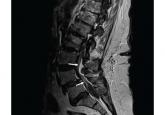

A 69-year-old woman with double vision and lower-extremity weakness

A middle-aged man with progressive neurologic deficits and bilateral leg lesions